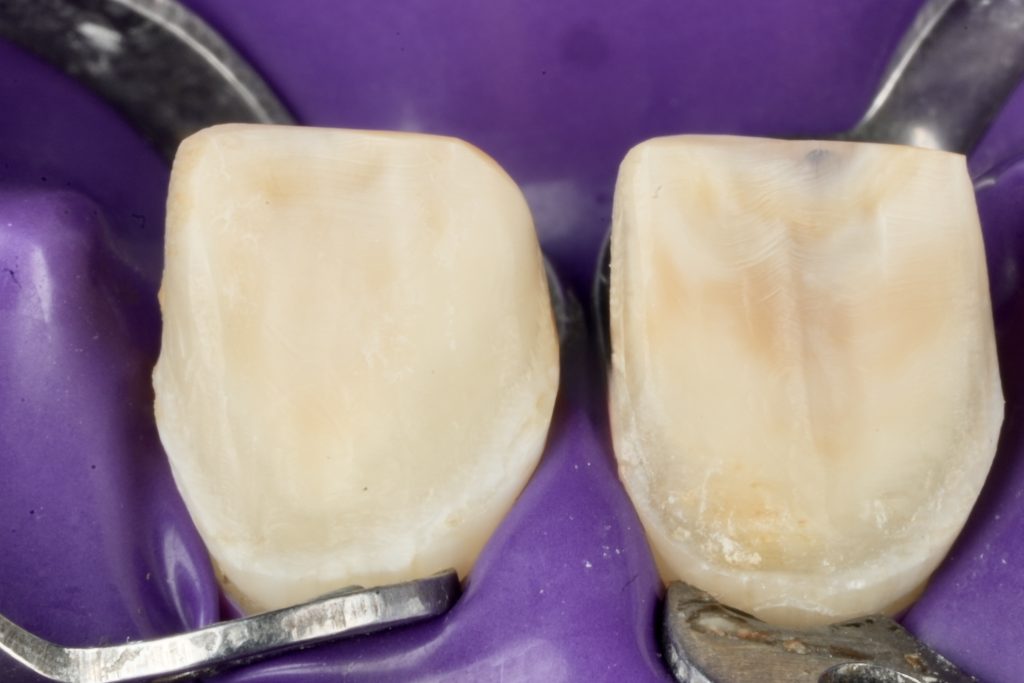

Using silicone indexes derived from the mock-up, controlled minimal-thickness veneer preparations (0.3–0.5 mm) were carried out under microscope magnification to ensure uniform reduction and margin clarity (Fig 2). Finish lines were placed juxta-gingivally with soft-tissue protection using Teflon and double-cord isolation.